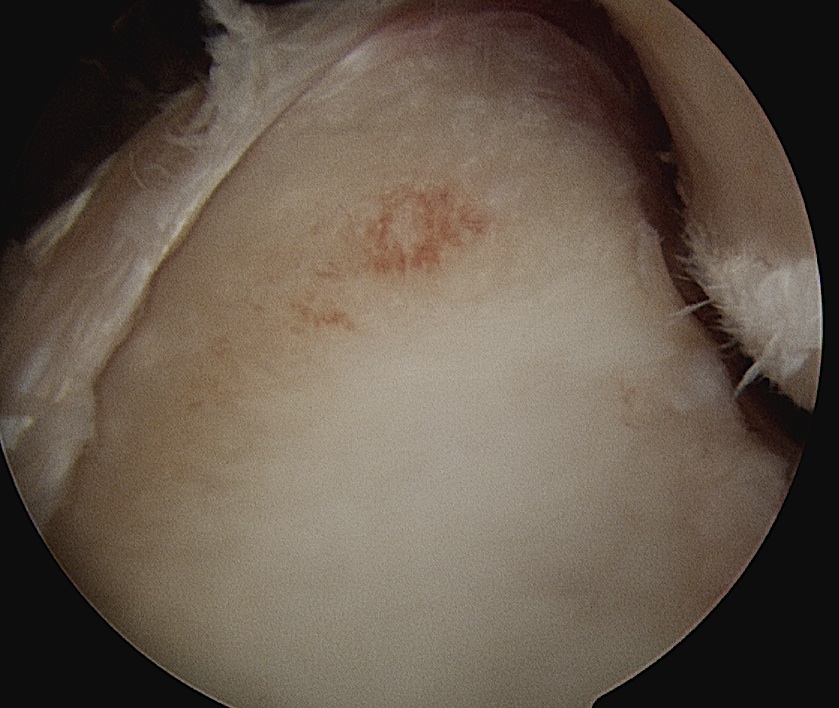

Hill Sachs lesion

Hill Sachs ArthroscopyShoulder Engaging Hill SachsHill sachs